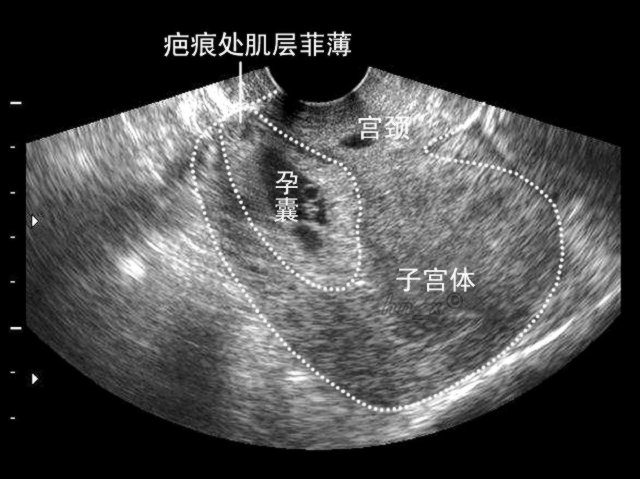

疤痕子宫怀孕前,除了常规的检查之外,还应当行子宫B超检查,以明确子宫疤痕处的肌层的厚度及连续性,评估是否适合怀孕。

疤痕子宫怀孕后,早期应当注意孕囊与疤痕的位置关系,警惕疤痕妊娠,中期应当注意胎盘与疤痕的位置关系,晚期应当特别留意子宫疤痕的厚度。